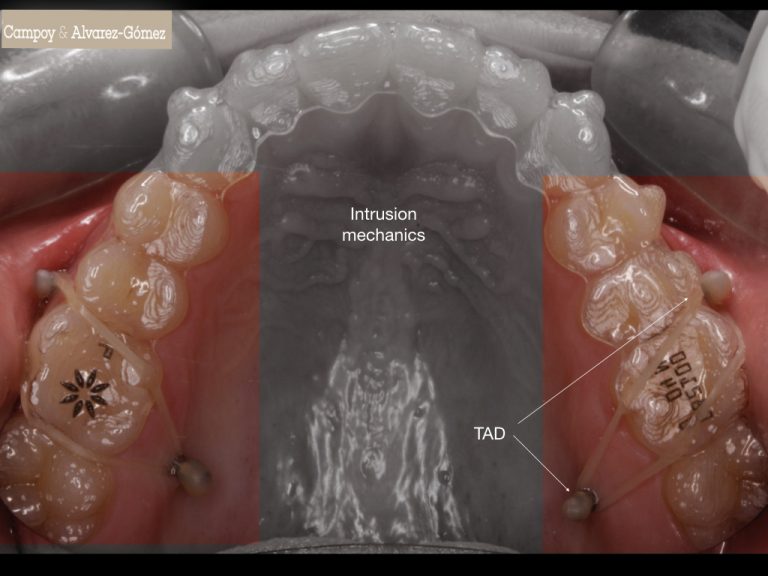

From campoyalvarezgomez.com

INTRUSIÓN INFERIOR CON MICROTORNILLOS (TADS) Clínica Dental Campoy What Are Dental Tads a temporary anchorage device works by creating a fixed anchor point that dental surgeons —often oral & maxillofacial surgeons — can use to. temporary anchorage devices (tads) serve as anchors to facilitate specific tooth movements in orthodontic treatment. Learn more about these devices and how. orthodontists use temporary anchorage devices (tads) alongside braces to correct oral issues.. What Are Dental Tads.

Control de mordida abierta con alineadores + TADS Clínica Dental What Are Dental Tads Their small size allows precise placement, enhancing treatment effectiveness. a temporary anchorage device (tad) is a device that is temporarily fixed to bone for the purpose of enhancing orthodontic. Learn more about these devices and how. temporary anchorage devices (tads) serve as anchors to facilitate specific tooth movements in orthodontic treatment. a temporary anchorage device works by. What Are Dental Tads.